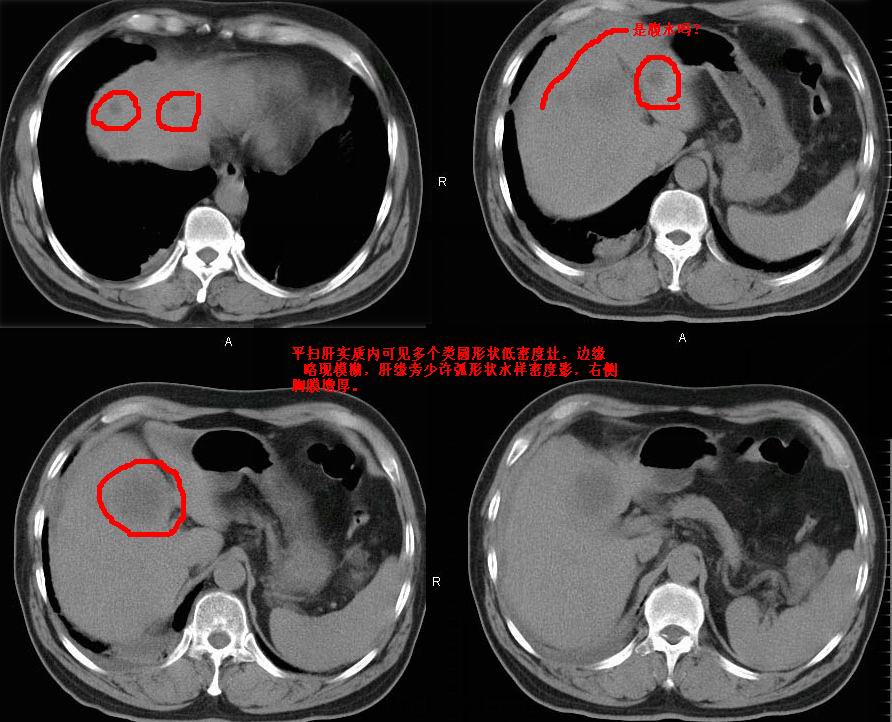

增强效果不理想。考虑转移,胆囊壁明显增厚,不排除胆囊癌肝转移。

病灶无强化,考虑囊肿。

增强效果不理想,考虑转移。

牛眼征,中心坏死无强化,外缘强化,最外缘又见低密度,考虑转移,与脓肿鉴别

考虑右肺下叶周围癌肝转移

肝内多发转移瘤,右下肺炎症并少量胸水。胃壁增厚建议胃镜,胰尾部“病变”为肠管。

肝内多发病灶,增强做的不太理想,效果欠佳,考虑是不是脓肿,看临床资料!!!!!!!

1)肝脏多发性转移瘤(不排除胰尾癌转移所致可能)。2)腹水。3)右侧少量胸腔积液。

增强效果太差了,是手推的吧,不会是团注的,肝内多发低密度灶占位,多考虑为肝ca

右下胸膜肥厚。

肝囊肿。

胰尾占位?结肠脾曲?